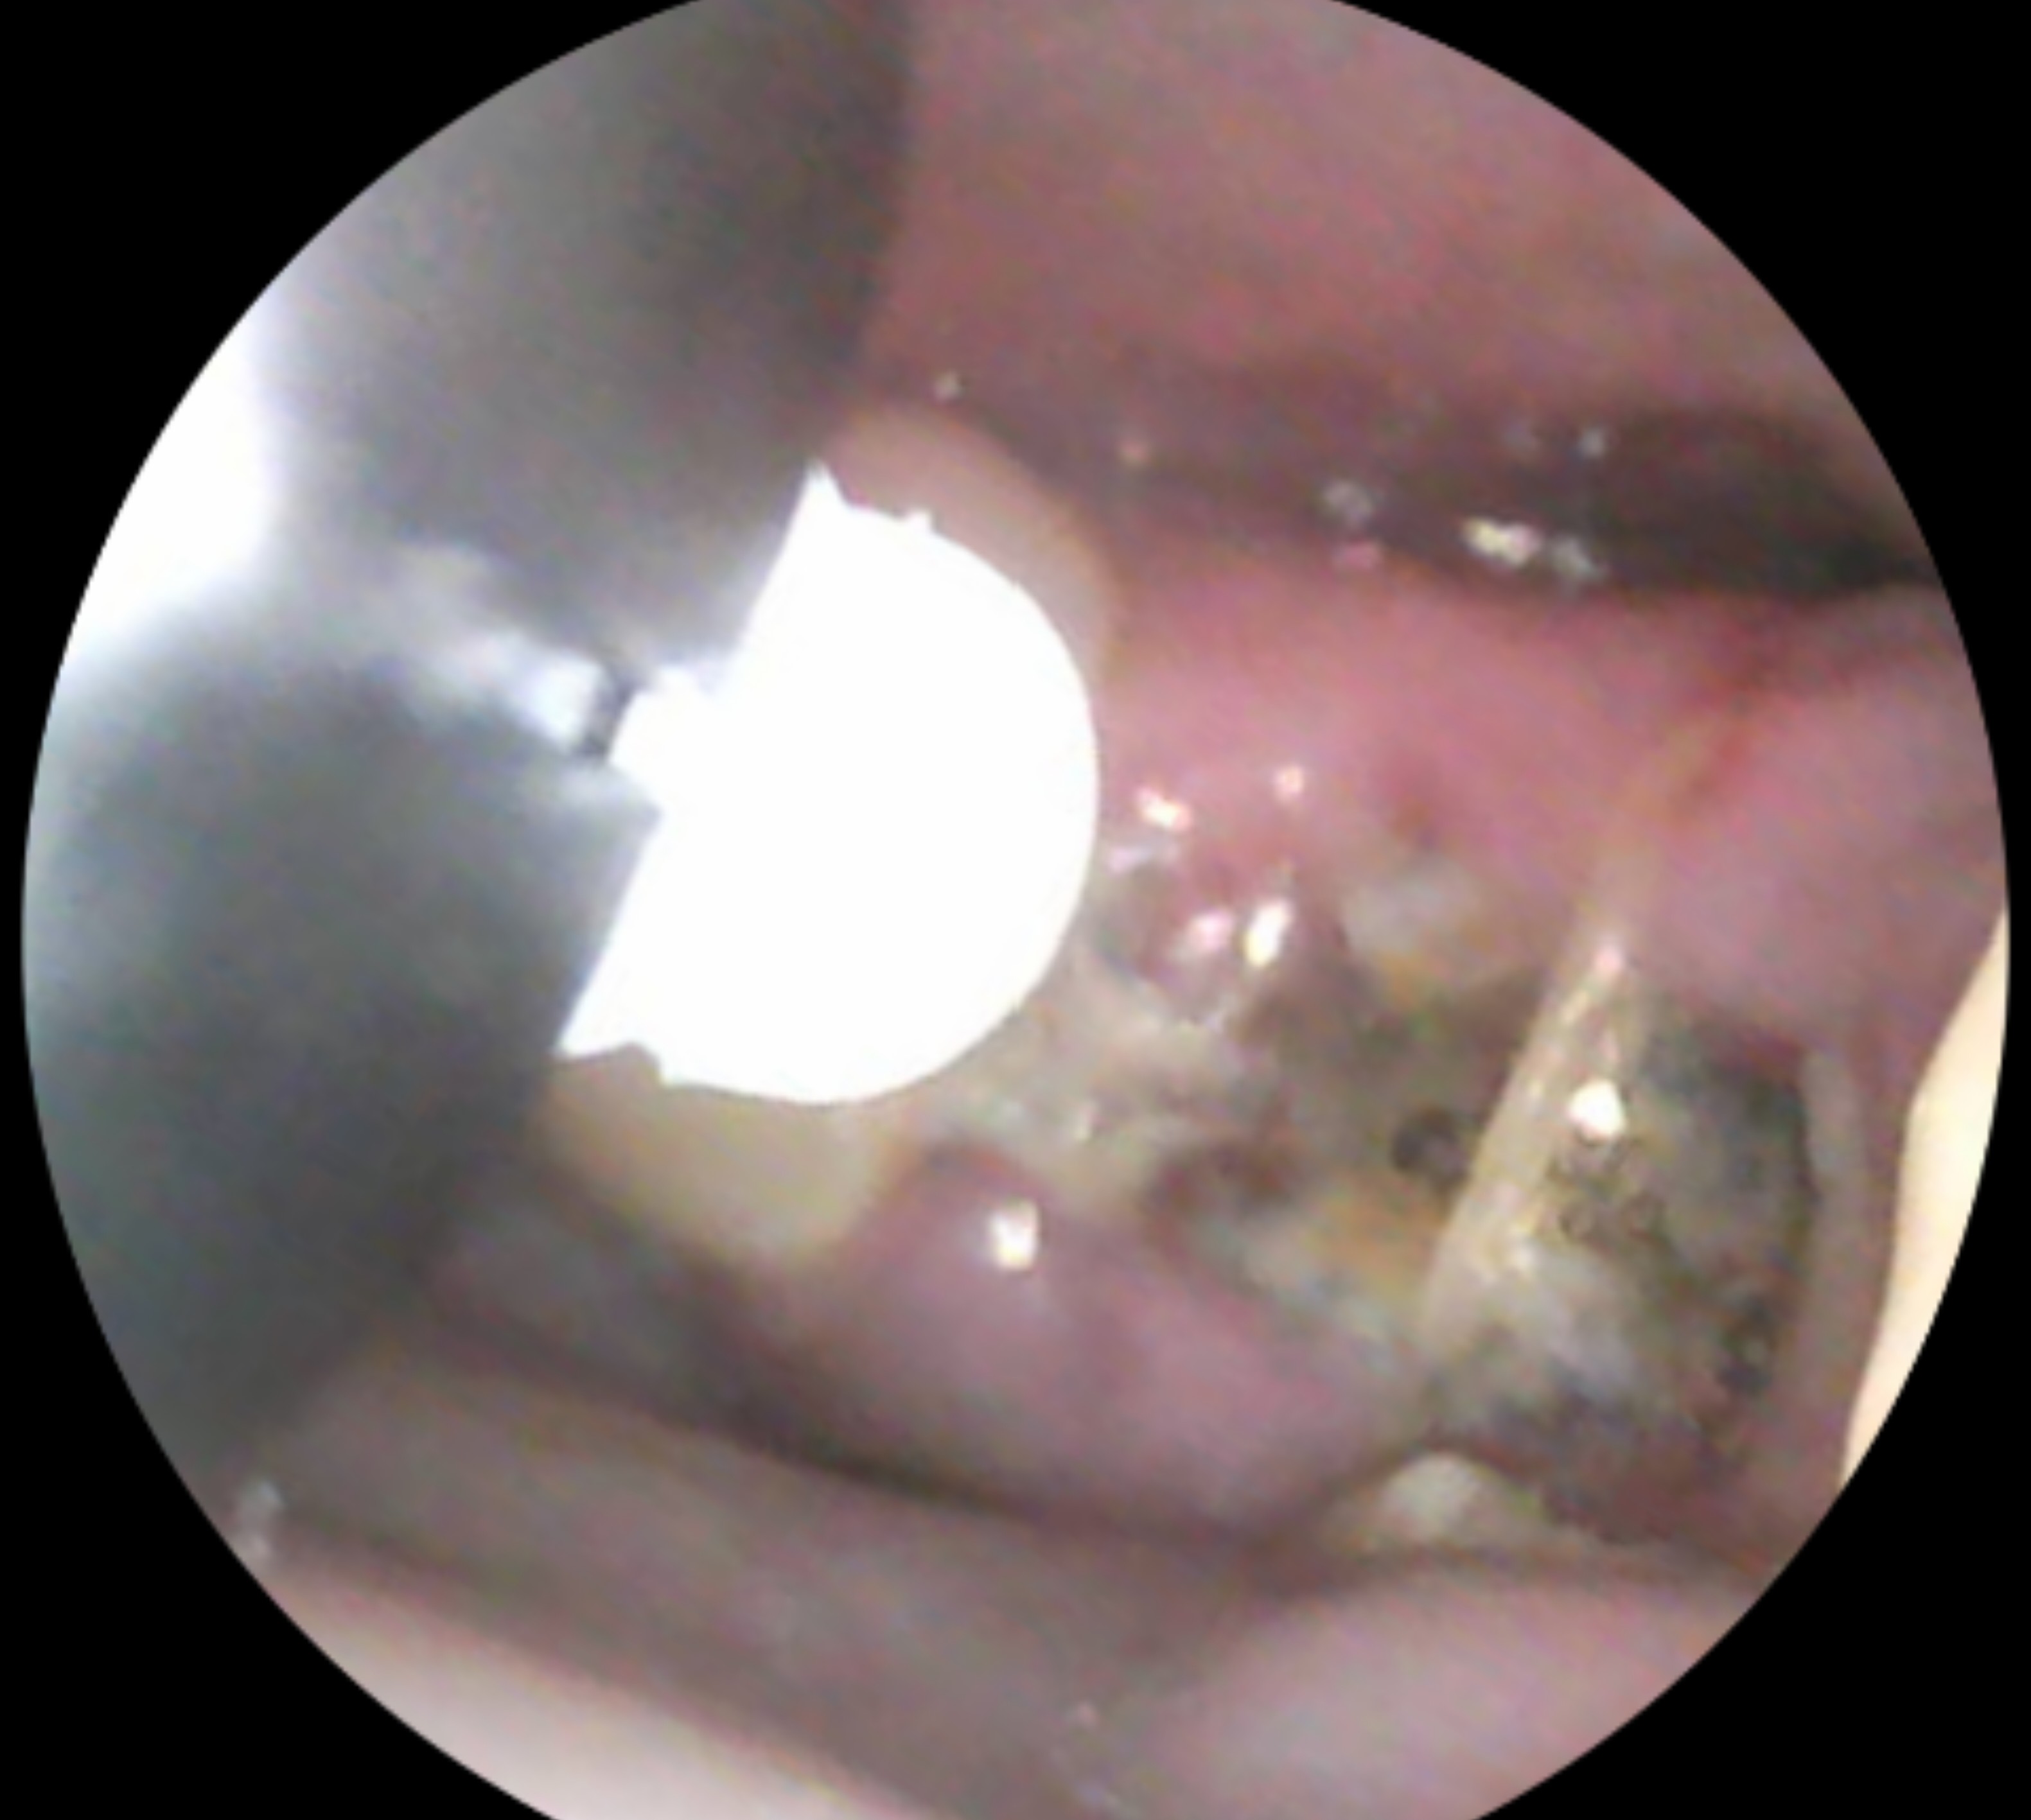

Wisdom teeth removed, is this dry socket or healing normally?

I’m concerned I have a dry socket from my salt rinses. Does this look like normal healing or is something wrong? It has a gray color and on the right side I can see some white. I got my teeth removed on 5/3 and felt like I was healing alright. I got...